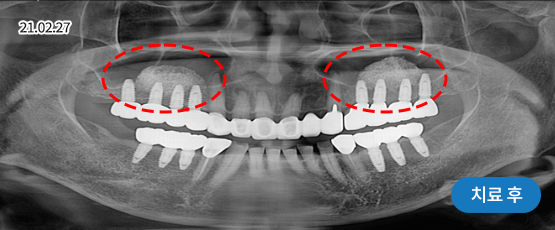

전악 임플란트

치아가 하나도 남아있지 않거나 전체적으로 상실된 경우 추천합니다.

치아의 기능을 다시 회복하기 위해 선택하는 임플란트입니다.

상실한 치아를 오랫동안 방치한 경우 상, 하악 잇몸뼈의 양도 부족한 경우가 많기 때문에 개개인의 건강 상태를 고려하여 정확한 수술 계획을 세워야 합니다.

• 치주질환으로 인해 음식을 씹기 힘들고,

미관도 좋지 않아 치아를 모두 발치한 후

전체 임플란트 수술을 하기로 결정

• 위 8개 + 아래 8개 임플란트 수술 진행 후

위 13개 + 아래 13개 (전체 치아)

임플란트 보철 제작 예정

• 임플란트 보철 완성